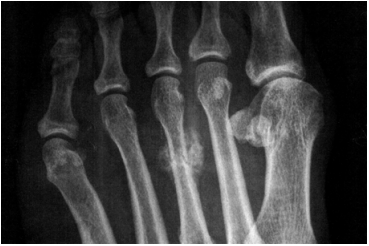

27 54 歲女性患者因右手指關節第 2, 3, 4 近端指關節(PIP)腫痛,右大指本節腫痛,頸肩酸痛,每天手 關節晨僵 2 小時等症狀已半年,至醫院就醫,實驗室檢查:RA factor:177 U/mL,CRP:3.99 mg/dL,下 列何者是最有可能的診斷? (A)退化性關節炎 (B)類風濕性關節炎 (C)痛風性關節炎 (D)創傷性關節炎

45 60 歲婦人,有高血壓病史,每天赤腳在紅土操場行走 2 小時,約有 6 個月之久,某天足背腫起疼痛,至診所 以外敷藥治療 2 星期之久,仍未消腫,至醫院 X 光檢 查如圖,則下列何項臆斷最為可能?

(A)骨膜骨肉瘤 (B)蹠骨骨折 (C)骨囊腫 (D)纖維瘤